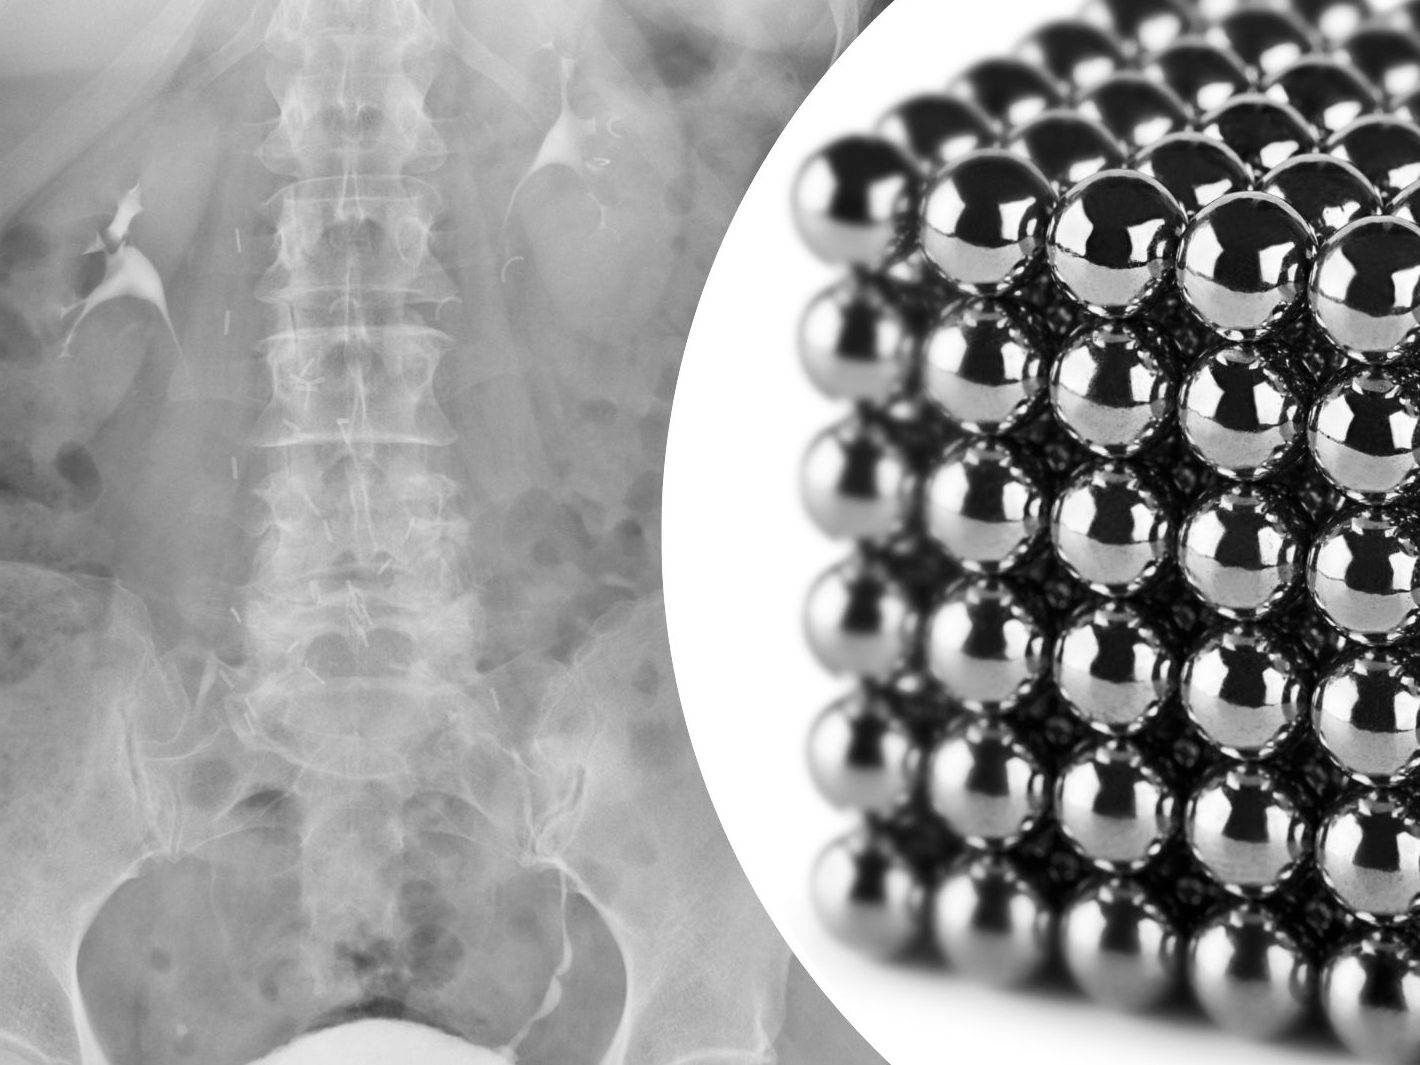

Die Magneten, die in Neuseeland seit Anfang 2013 verboten seien, seien auf der Temu-Plattform gekauft worden, teilten die Ärzte mit. Eine Röntgenaufnahme habe gezeigt, dass die Magneten sich in verschiedenen Bereichen des Darms aufgrund der Anziehungskraft zu vier geraden Linien zusammenklumpten. Den Ärzten zufolge starb durch die Kraft der Magneten an vier Stellen im Dünn- und Dickdarm Gewebe ab.